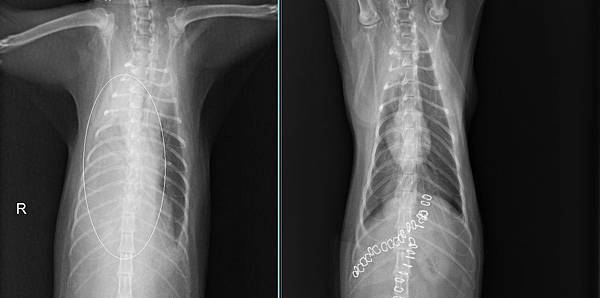

Cleo是一位九個月大的小朋友,媽媽遠從苗栗來找小譚醫師,說Cleo被檢查到橫膈膜破裂,肝臟掉到胸腔扭轉,肝指數已經高到驗血儀器檢查不出來了。

這已經屬於非常嚴重的情況,醫療團隊感快安排手術,手術發現,Cleo已經出血很嚴重血腹,肝臟也整個在胸腔打結,所幸在通力協助下,把破洞的橫膈膜仔細修補,肝臟也解開打結放回原本的位置。Cleo很爭氣的恢復很好,今天回來拆線也都一切正常。